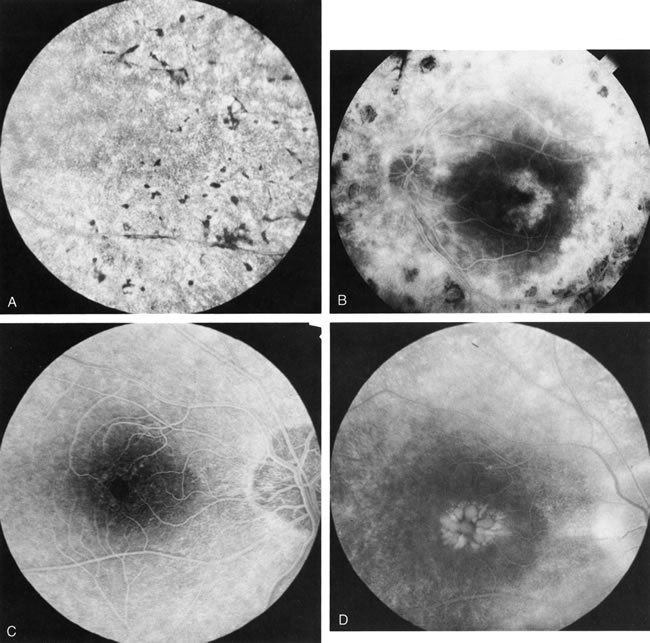

In retinitis pigmentosa (RP), the pigment abnormalities of atrophy, migration, and clumping are made apparent by transmitted hyperfluorescence and blocked hypofluorescence (Fig. 1A). Patients who have very minimal pigmentary alterations (pauci pigmentary RP) or no pigment abnormalities (RP sine pigmento) may show the abnormalities on fluorescien angiography (FA). It is uncommon to see choriocapillaris atrophy except in the late stages. This finding corresponds to the histopathology, which shows that the earliest abnormalities are in the photoreceptors and that the choroid is normal.1

Dye leakage in RP may occur from the retinal vessels or at the level of the retinal pigment epithelium (Fig. 1B).2–4 The leakage may be seen in the macula and posterior pole, along the vascular arcades in the distribution of the radial peripapillary capillaries, and in the periphery (where an exudative vasculopathy resembling Coats' disease is suggested).

Of more clinical importance is the role of FA in the diagnosis and treatment of cystoid macular edema (CME) (Fig. 1C and D). Stereoscopic FA indicates that the leakage, which may be diffuse or have the typical petaloid stellate appearance of CME, can come from the perifoveal retinal capillaries, from the choroid through the RPE, or from a combination of both sources.4 With the recent suggestion that CME in RP may be successfully treated with acetazolamide,5, 6 FA is thus important to document the diagnosis of CME, establish the origin(s) of leakage, and follow patients during and after therapy.